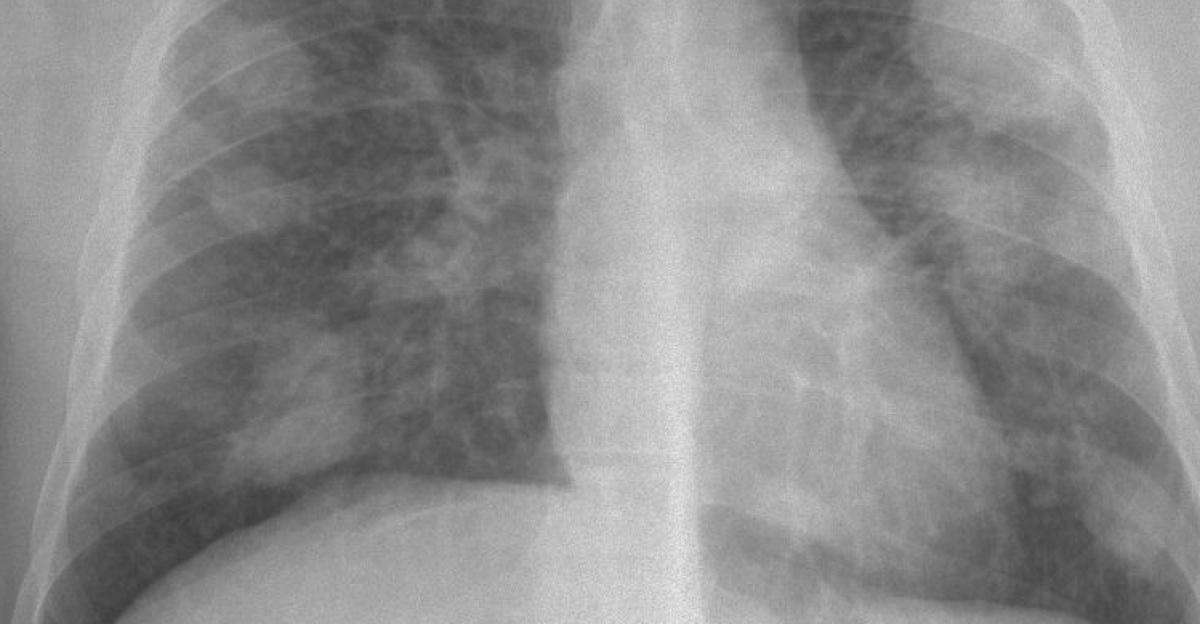

What Silicosis Does to the Body

Silicosis causes progressive lung tissue scarring. Early symptoms include a persistent cough, mucus production, and shortness of breath.

As the disease advances, patients suffer fatigue, chest pain, swollen legs, and bluish lips from oxygen loss. Silicosis increases the risk for lung cancer, tuberculosis, and high blood pressure.

Once silicosis develops, options shrink, and outcomes worsen. Stage one patients live 20 to 27 years, stage two patients live 16 to 20 years, and stage three patients live 7 to 11 years.

Early detection through chest X-rays or CT scans extends survival by years. Most cases are diagnosed at late stages, after irreversible damage has occurred.